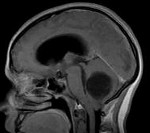

Затруднения в диагностике гемангиобластомы связаны с неспецифичностью ее клинических проявлений, маскировкой неврологического дефицита и мозжечкового синдрома под выраженной общемозговой симптоматикой. Тщательный неврологический осмотр и дополнительная консультация офтальмолога, в ходе которой выявляются застойные диски зрительных нервов, позволяют заподозрить наличие внутричерепного объемного образования. При этом, кроме обычного первичного обследования в виде ЭЭГ, РЭГ и Эхо-ЭГ, пациенту в обязательном порядке должно быть проведено МРТ головного мозга.

В большинстве случаев исследование послойных горизонтальных и сагиттальных срезов, полученных при проведении МРТ, позволяет установить локализацию опухолевого процесса и дифференцировать его от абсцесса головного мозга, внутримозговой гематомы, очага демиелинизации при рассеянном склерозе, последствий тяжелой черепно-мозговой травмы, кисты головного мозга Окончательная диагностика гемангиобластомы и определение ее микроскопического типа возможны лишь после гистологического изучения образца опухоли. Необходимые для исследования опухолевые ткани могут быть получены в результате стереотаксической биопсии мозга или в ходе операции по удалению опухоли.